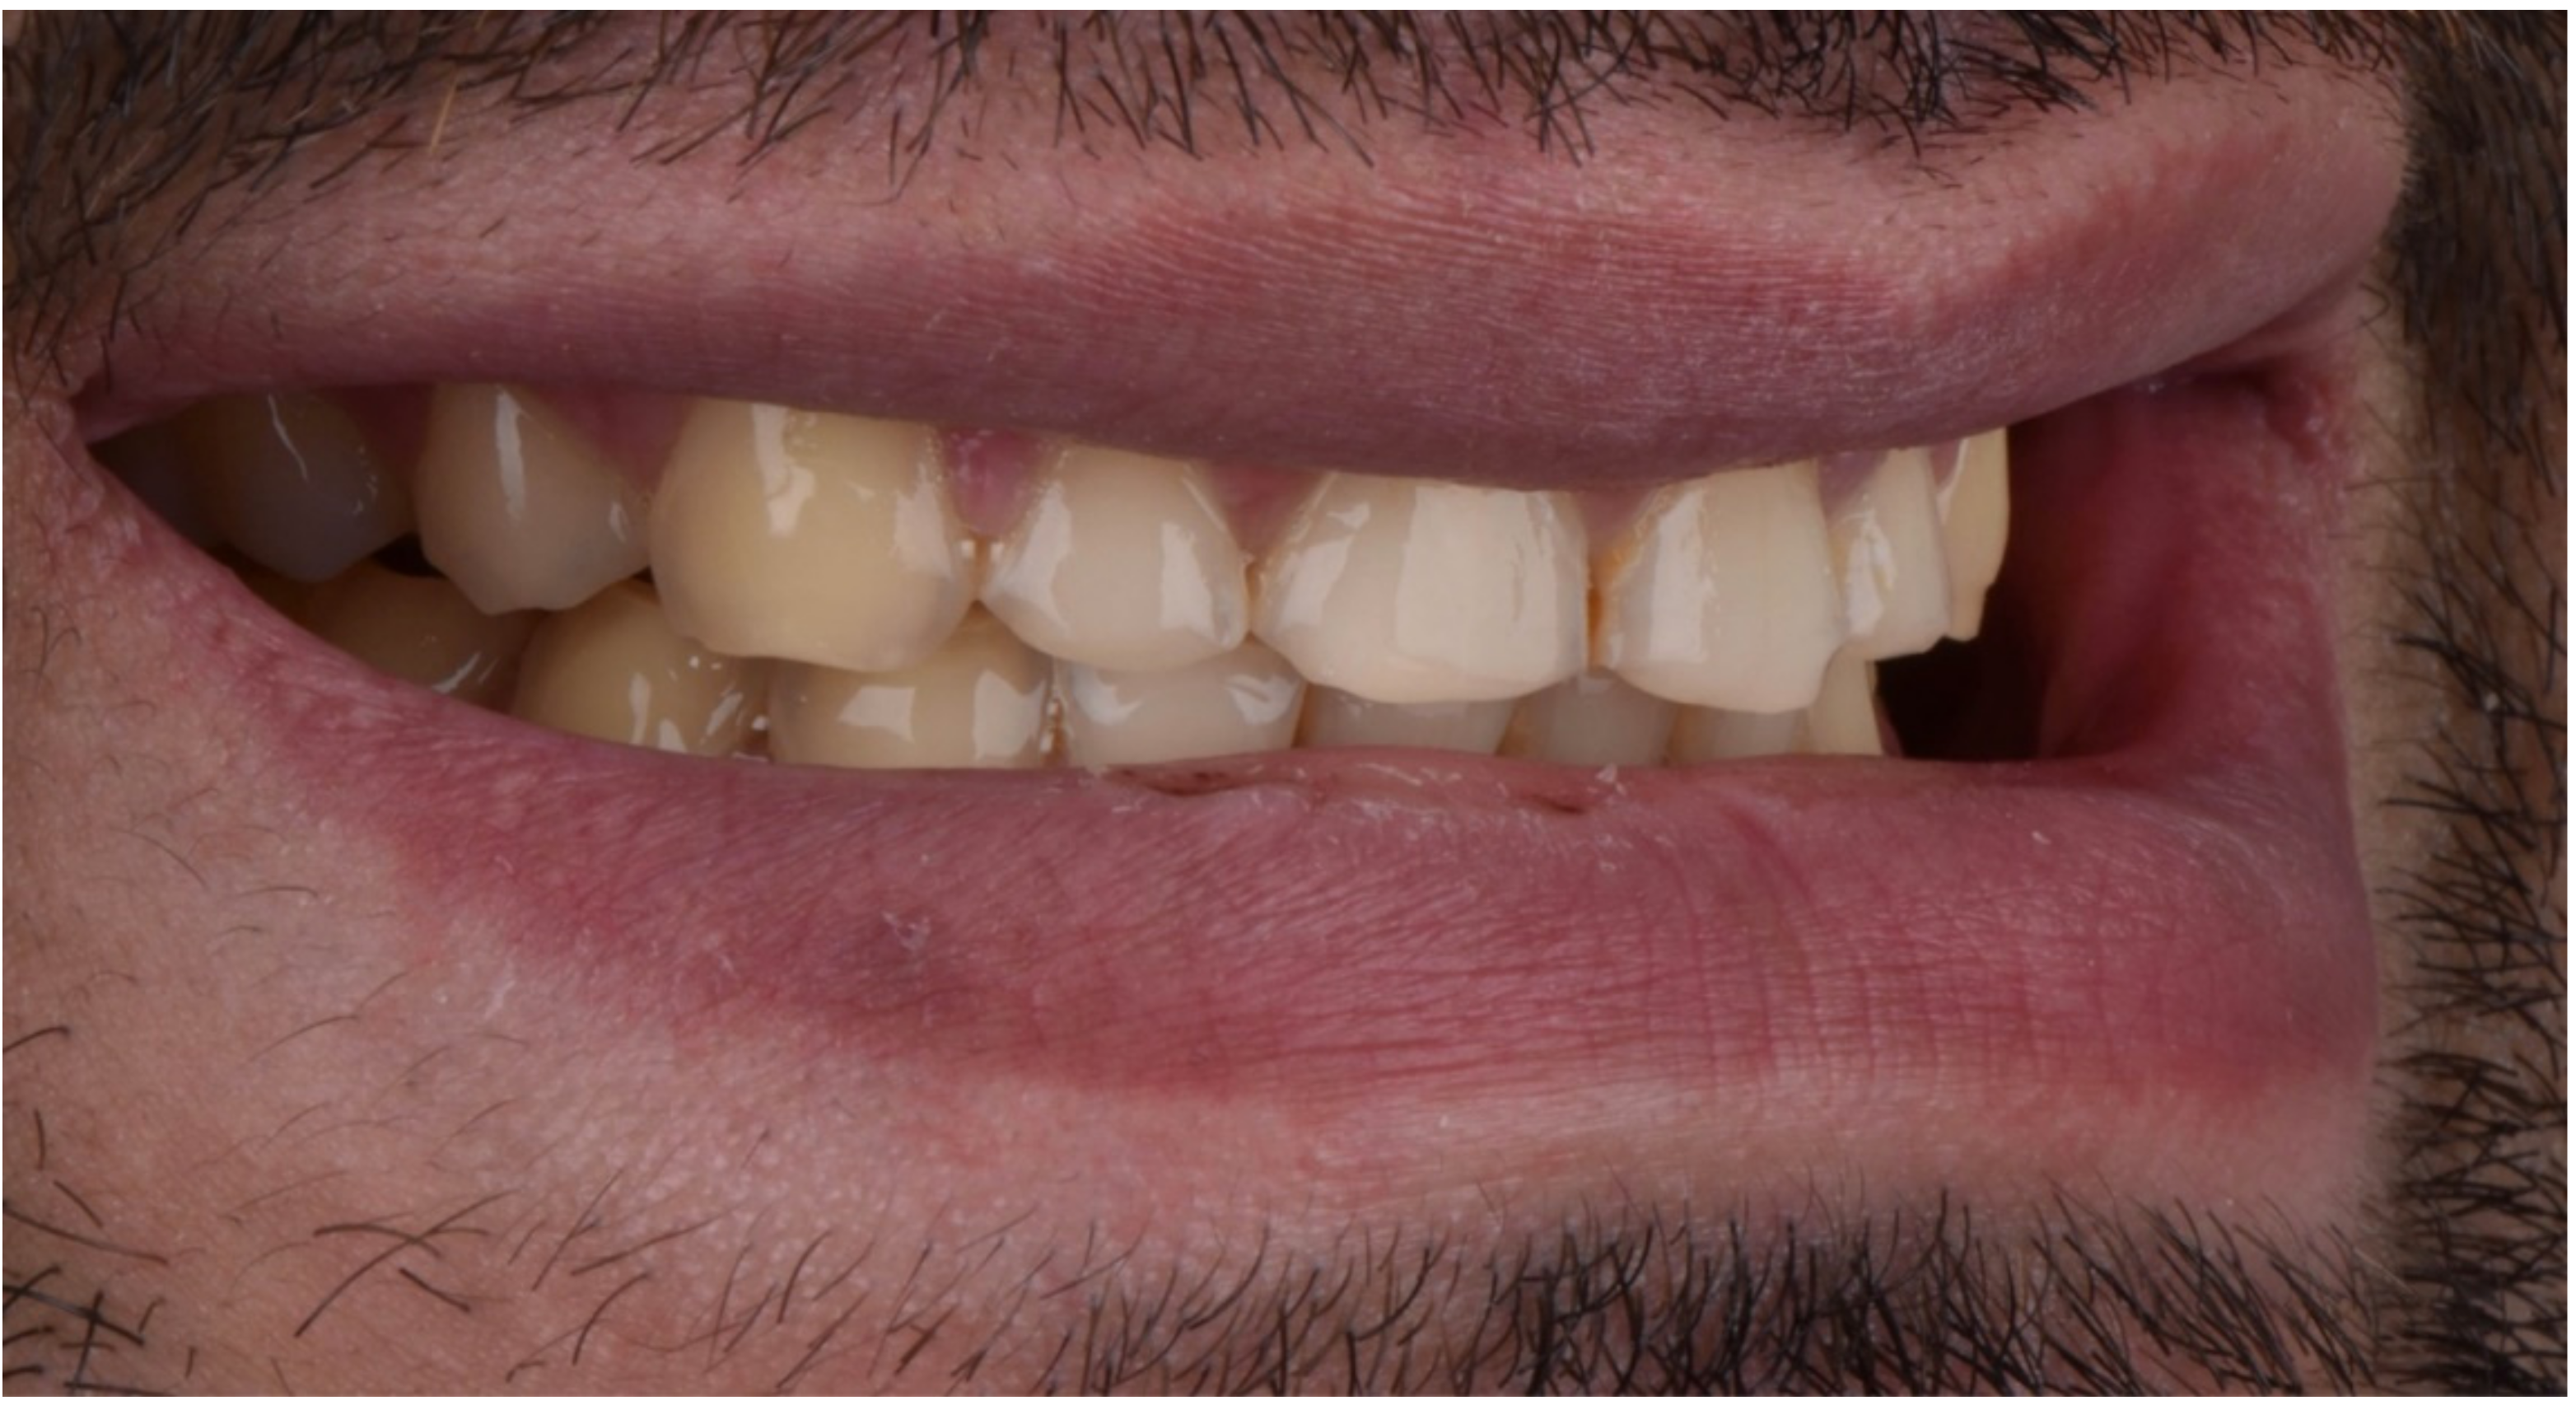

2.2. Restorative Phase